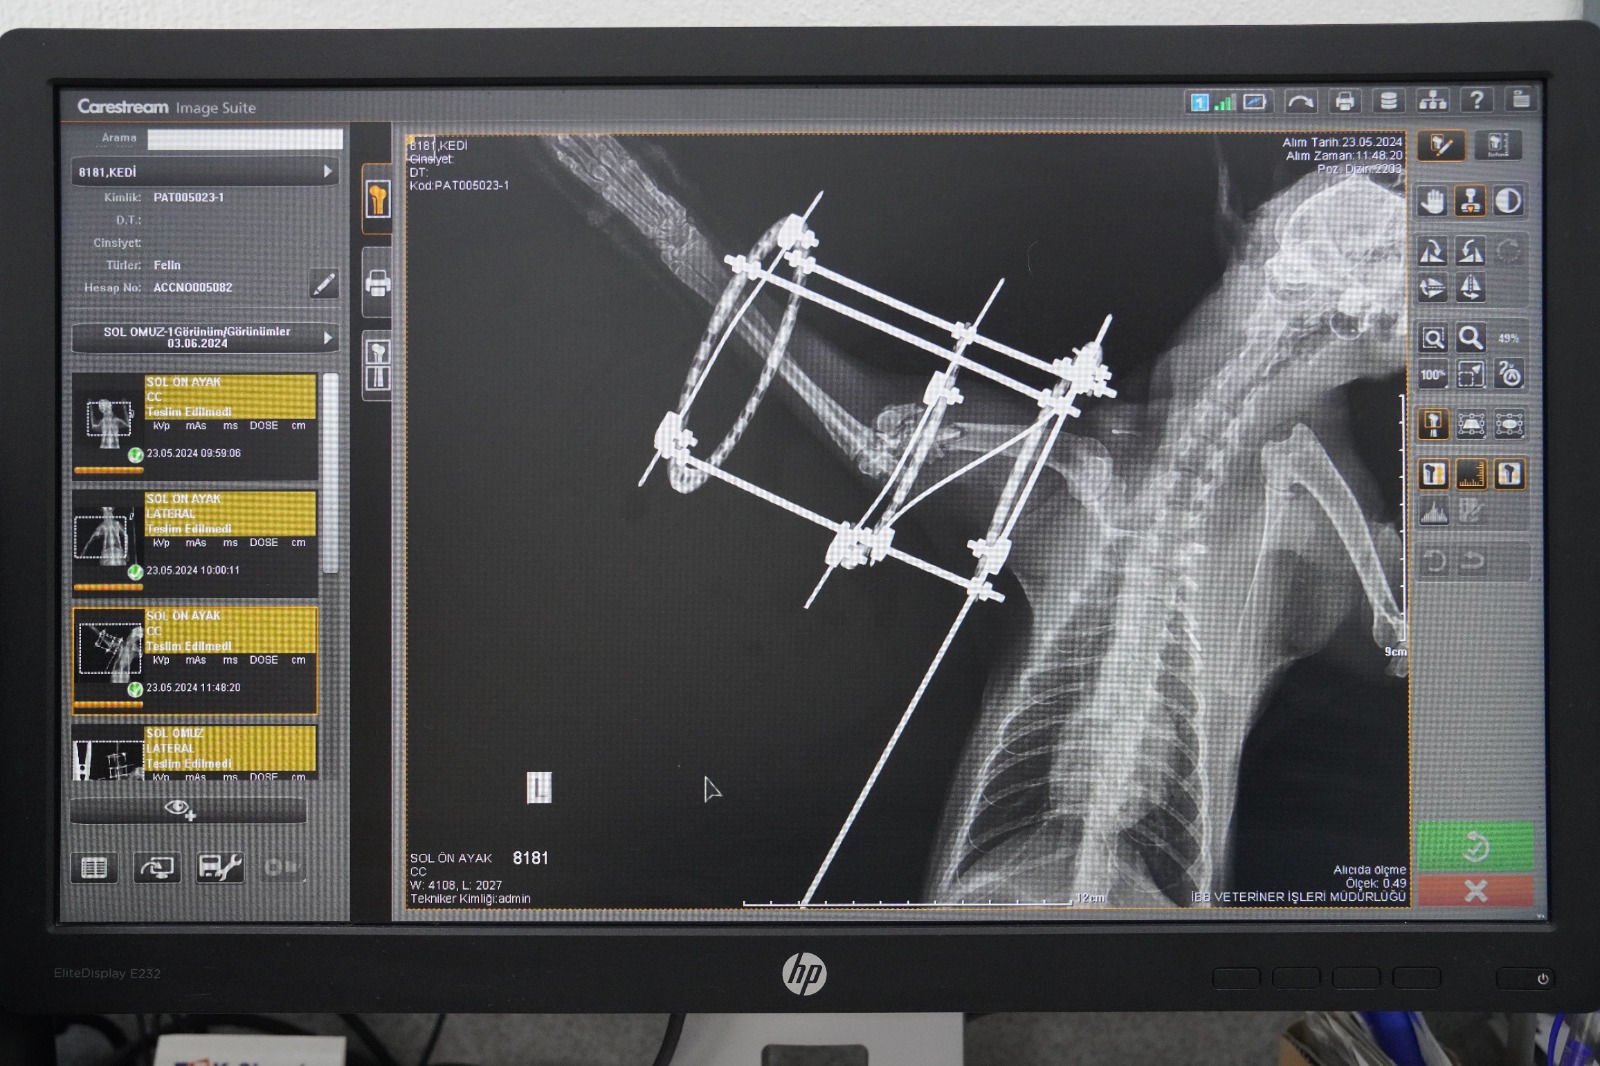

Ameliyat hakkında bilgi veren Veteriner Hekim Mehmet Uysal, ortopedi biriminde kedinin bacağının durumunu tespit ettiklerini belirterek, “Bacağının ciddi şekilde parçalandığını gördük. Burada sağlığına kavuşması için hemen gerekli cerrahi tedaviyi uyguladık. Bacağında parçalanan kemikleri özel bir aparatla sabitledik.

Güvenli bir yöntem olduğu için bunu tercih ettik. Kedimiz 25 gündür bu şekilde tedavi altında. Bir süre sonra bu taktığımız aparatın kırıklar üzerindeki etkisine bakacağız. Bacak iyileşmiş olursa çıkaracağız. Şu anda sağlığı ile alakalı bir problemi yok. Keyfi yerinde. Bacağını nasıl kullanacağını öğreniyor diyebilirim” diye konuştu.

Bu yöntemin zorlu ve maliyetli olduğunu da aktaran Uysal, “Biz böyle bir tedavi uygulamamış olsaydık kedinin bacağını ampute etmek zorunda kalacaktık. Çünkü iyileşme olasılığı çok düşük bir kırık. Biz bu şekilde şans vermek istedik. O da bizim tedavimize çok güzel bir şekilde cevap verdi. Muhtemelen de iyileşip buradan gidecek. En büyük temennimiz kendisine yuvasının kapısını açacak iyi yürekli bir aileyle birlikte buradan ayrılması” dedi.